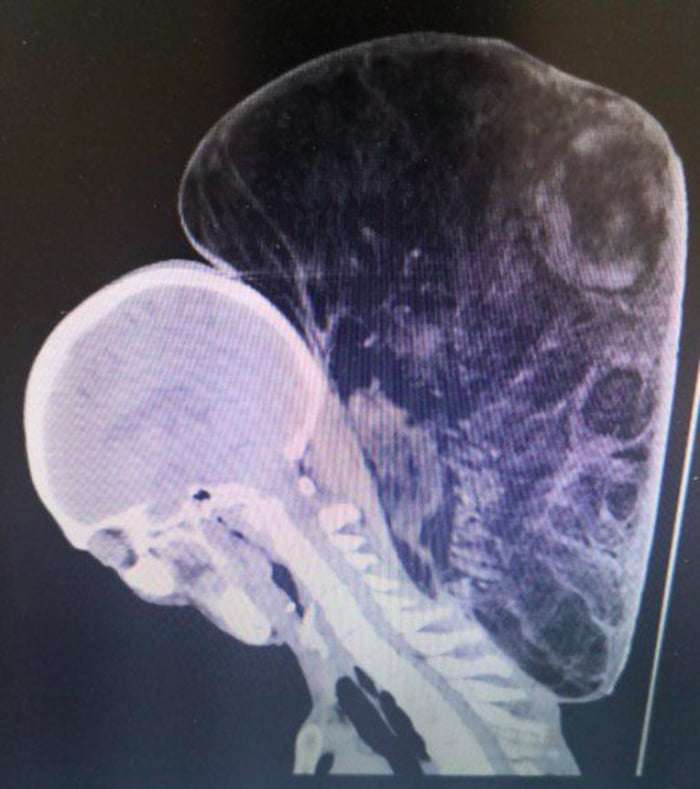

15公斤腫瘤如影隨行47年 醫生花10小時幫他移除「瞬間超不習慣」

2018年06月04日大陸貴州有一位64歲的趙姓老伯,他17歲時頸上出現一個腫瘤,腫瘤越長越大,足足長到了15公斤。這麼多年來,他一直背著這個沉重的負擔生活。最近,他終於解脫了。

▼趙老伯表示,他17歲時頸上出現了腫瘤,剛開始只是雞蛋大小,因為不疼不癢,他就沒有在意。隨著時間的推移,腫瘤越來越大,開始影響他的生活。他只能側身睡覺,沒辦法穿套頭衣物,洗澡也需要家人幫忙。

▼趙老伯家經濟條件不好,一直沒有接受治療,但頭頸托著15公斤的重量,真的太吃力了。眼看腫瘤越變越大,孩子們擔心他受不了,這才籌錢帶他去看病。醫生看到後驚呼:「我工作這麼多年,從來沒見過這麼大的腫瘤!」

▼貴州省腫瘤醫院綜合外科副主任董世祥表示,趙老伯頸上的腫瘤,初步診斷是脂肪瘤。「患者的情況不是典型的脂肪瘤,並不是每個人的脂肪瘤都會長這麼大,還是要視個人情況而定。」

▼經過10個小時的手術,醫生幫趙老伯切除95%的腫瘤,他終於不用再受苦了。

背負了47年的負擔一下子卸掉,趙老伯還有點不習慣。沒有腫瘤的束縛,他的生活終於回到正軌了~